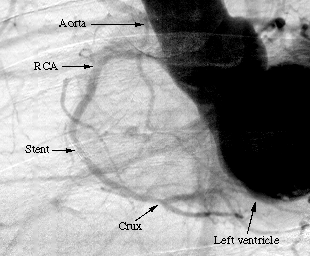

For the first patients, we obtained a good agreement in terms of stenosis diagnosis between synchrotron angiography and the usual angiography procedure in hospital. One image obtained with the first patient at the ESRF is shown on Figure 1a. Stenosis appears visible inside the stent in the second segment C2, and the known distal stenosis visible at the crux remains mild (inferior to 50%). We stress the excellent visualization of the distal part of the right coronary artery (RCA). These findings were in excellent agreement with the conventional selective coronarography perfomed few hours later in the hospital cardiological unit (Figure 1b).

b: Conventional selective coronary angiography of the same patient, in the LAO orientation, performed the same day at the cardiological unit of the hospital after arterial catheterization.